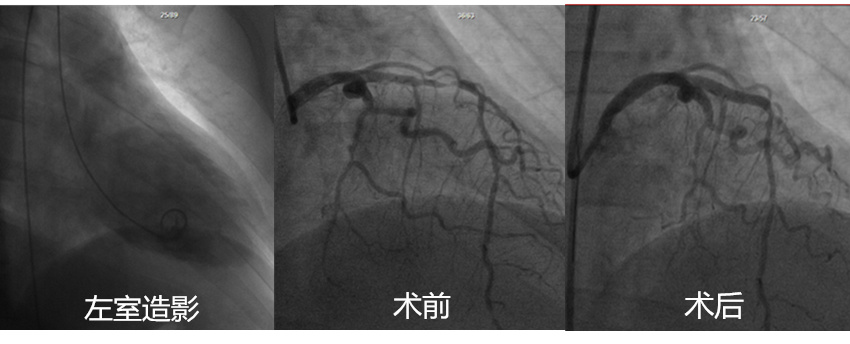

我院心内三科于2月18日上午开展首次冠脉介入手术,并顺利完成4例冠脉造影检查,其中包括2例支架植入术,及独立完成1例左室造影及左心导管检查。

在“患者安全第一”的宗旨下,为保证此次手术的成功开展,心内三科做了大量的前期工作,不仅对手术患者病情进行全方位监测,还在设备药品配置、消毒管理、人员培训等方面都做了充分的准备。手术全程由心内三科郑崔成主治医师施术、钍戈医师辅助独立完成,并邀请北大医院郑博教授在旁指导,为手术的顺利开展保驾护航。此次开展虽有波折,但仍圆满完成,其中两名患者射血分数较低,EF分别为30%及38%。至此,心内三科首次冠脉介入手术成功开展!